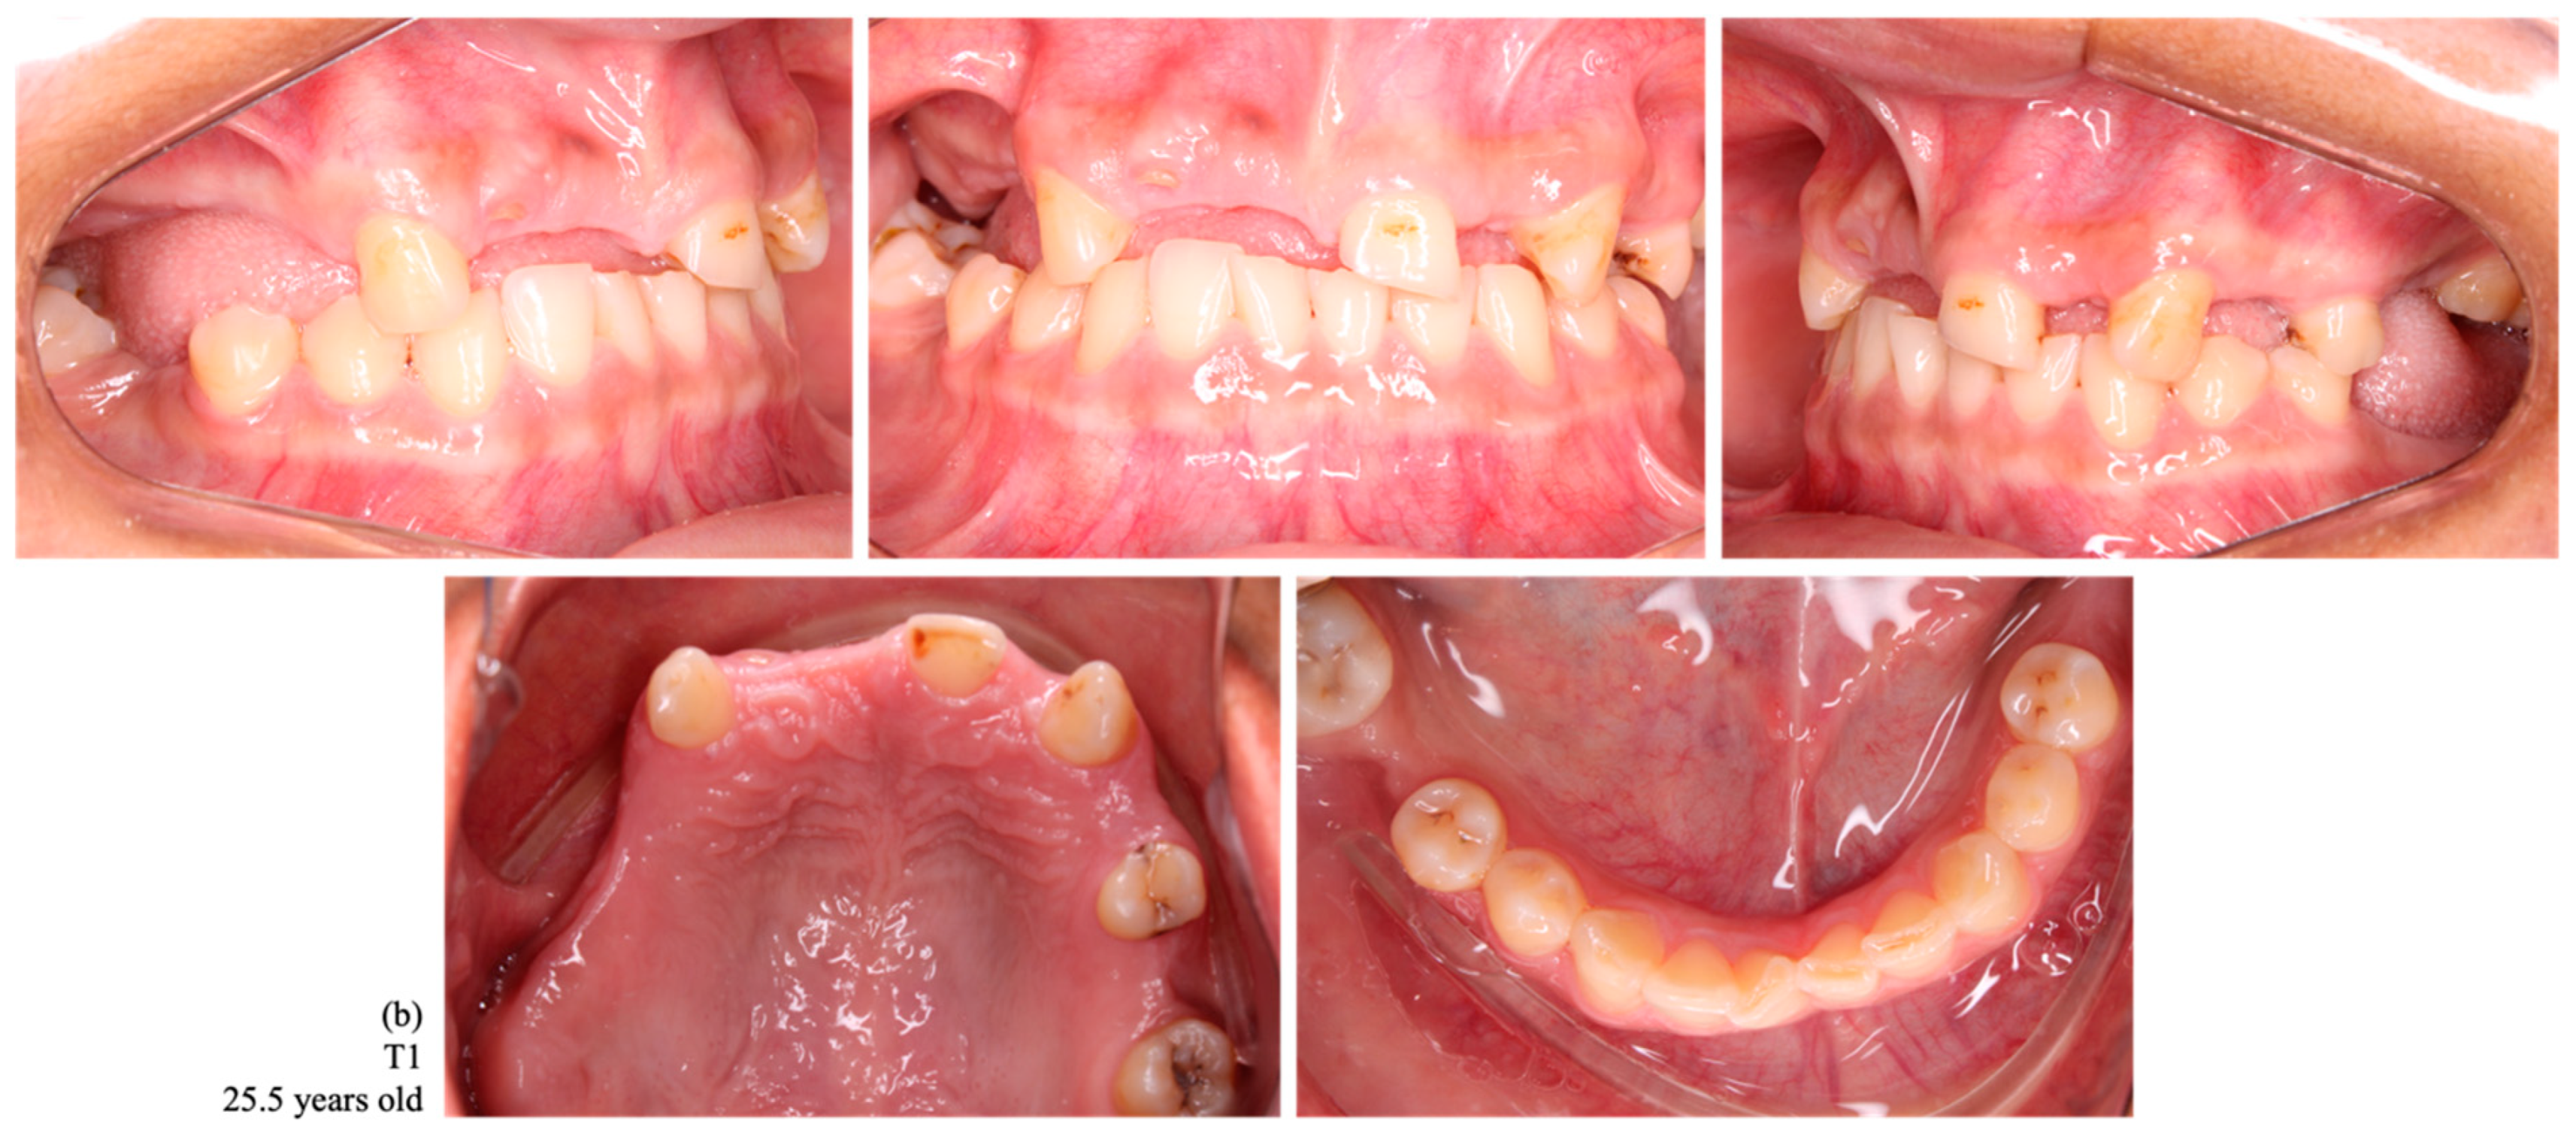

Figure 3.

Intraoral photographs of dental occlusion of a female indigenous participant, a habitant of the Arara village, with no tooth loss at T0 (a) and with a loss of 12 permanent teeth at T1 (1.7, 1.6, 1.5, 1.4, 1.2, 1.1, 2.2, 2.4, 2.6, 3.7, 3.6, and 4.6) (b).